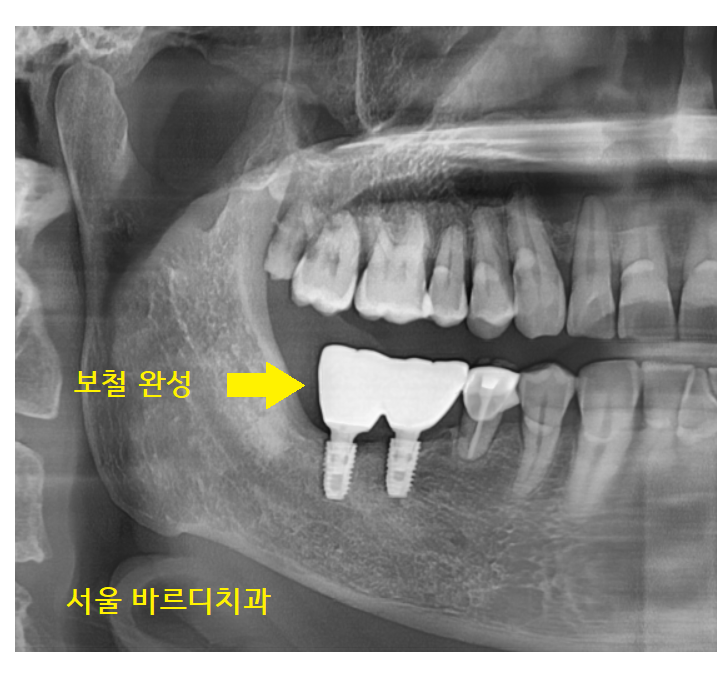

23.07.17

시간이 지나 맞춤 기둥 제작을 위한

뽄도 뜨고~~

24.03.06

보철도 예쁘게 만들어드렸습니다.

브릿지를 임플란트로 교체하였기에

씹는 힘은 훨씬~ 좋아지셨을 겁니다.